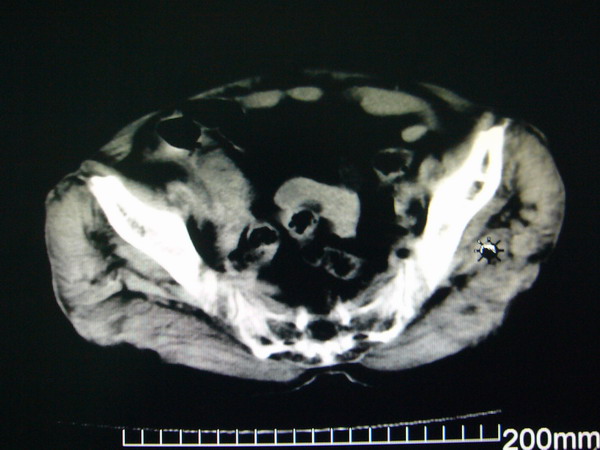

女:83y,转移性右下腹痛2小时,白细胞计数增高。

1.右侧肾盂扩大,肾盏无扩张,考虑:先天性肾盂变异可能性大。

2.胆囊扩张,考虑:胆囊炎。

3.阑尾区域可见以结节样高密度影,结合病史,考虑:阑尾结石,阑尾炎。

右下腹肠系膜增厚,结合病史支持阑尾炎.

右侧壶腹型肾盂可能,建议输路造影或增强

1.右侧肾盂扩大,考虑先天性肾盂变异或肾盂旁囊肿。

2.胆囊扩张,考虑胆囊炎。

3.阑尾区域可见结节样高密度影,结合病史考虑:阑尾结石、阑尾炎。